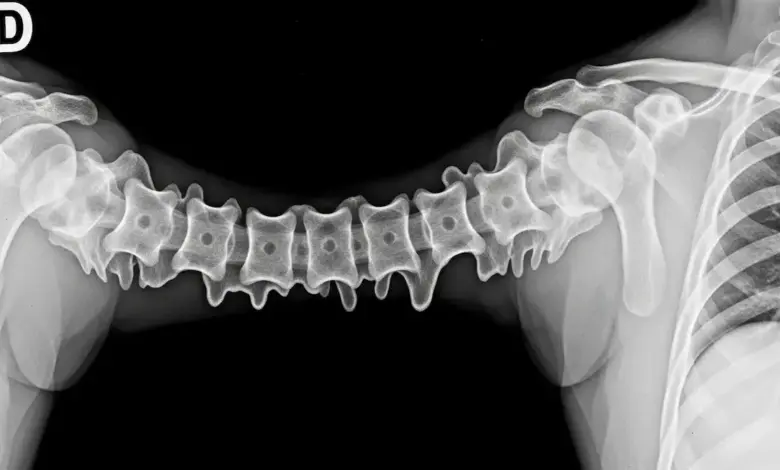

Na hiperostose esquelética idiopática difusa, forma-se “osso novo” ao longo da face ântero-lateral da coluna, muitas vezes com aspecto contínuo em vários níveis vertebrais.

Em critérios clássicos, descreve-se ossificação “fluida” envolvendo pelo menos quatro vértebras contíguas, com preservação relativa do espaço discal e sem sinais típicos de inflamação erosiva nas articulações sacroilíacas.

O diagnóstico é fortemente baseado em imagem, principalmente radiografia e tomografia quando necessário para detalhar ossificações e avaliar complicações.